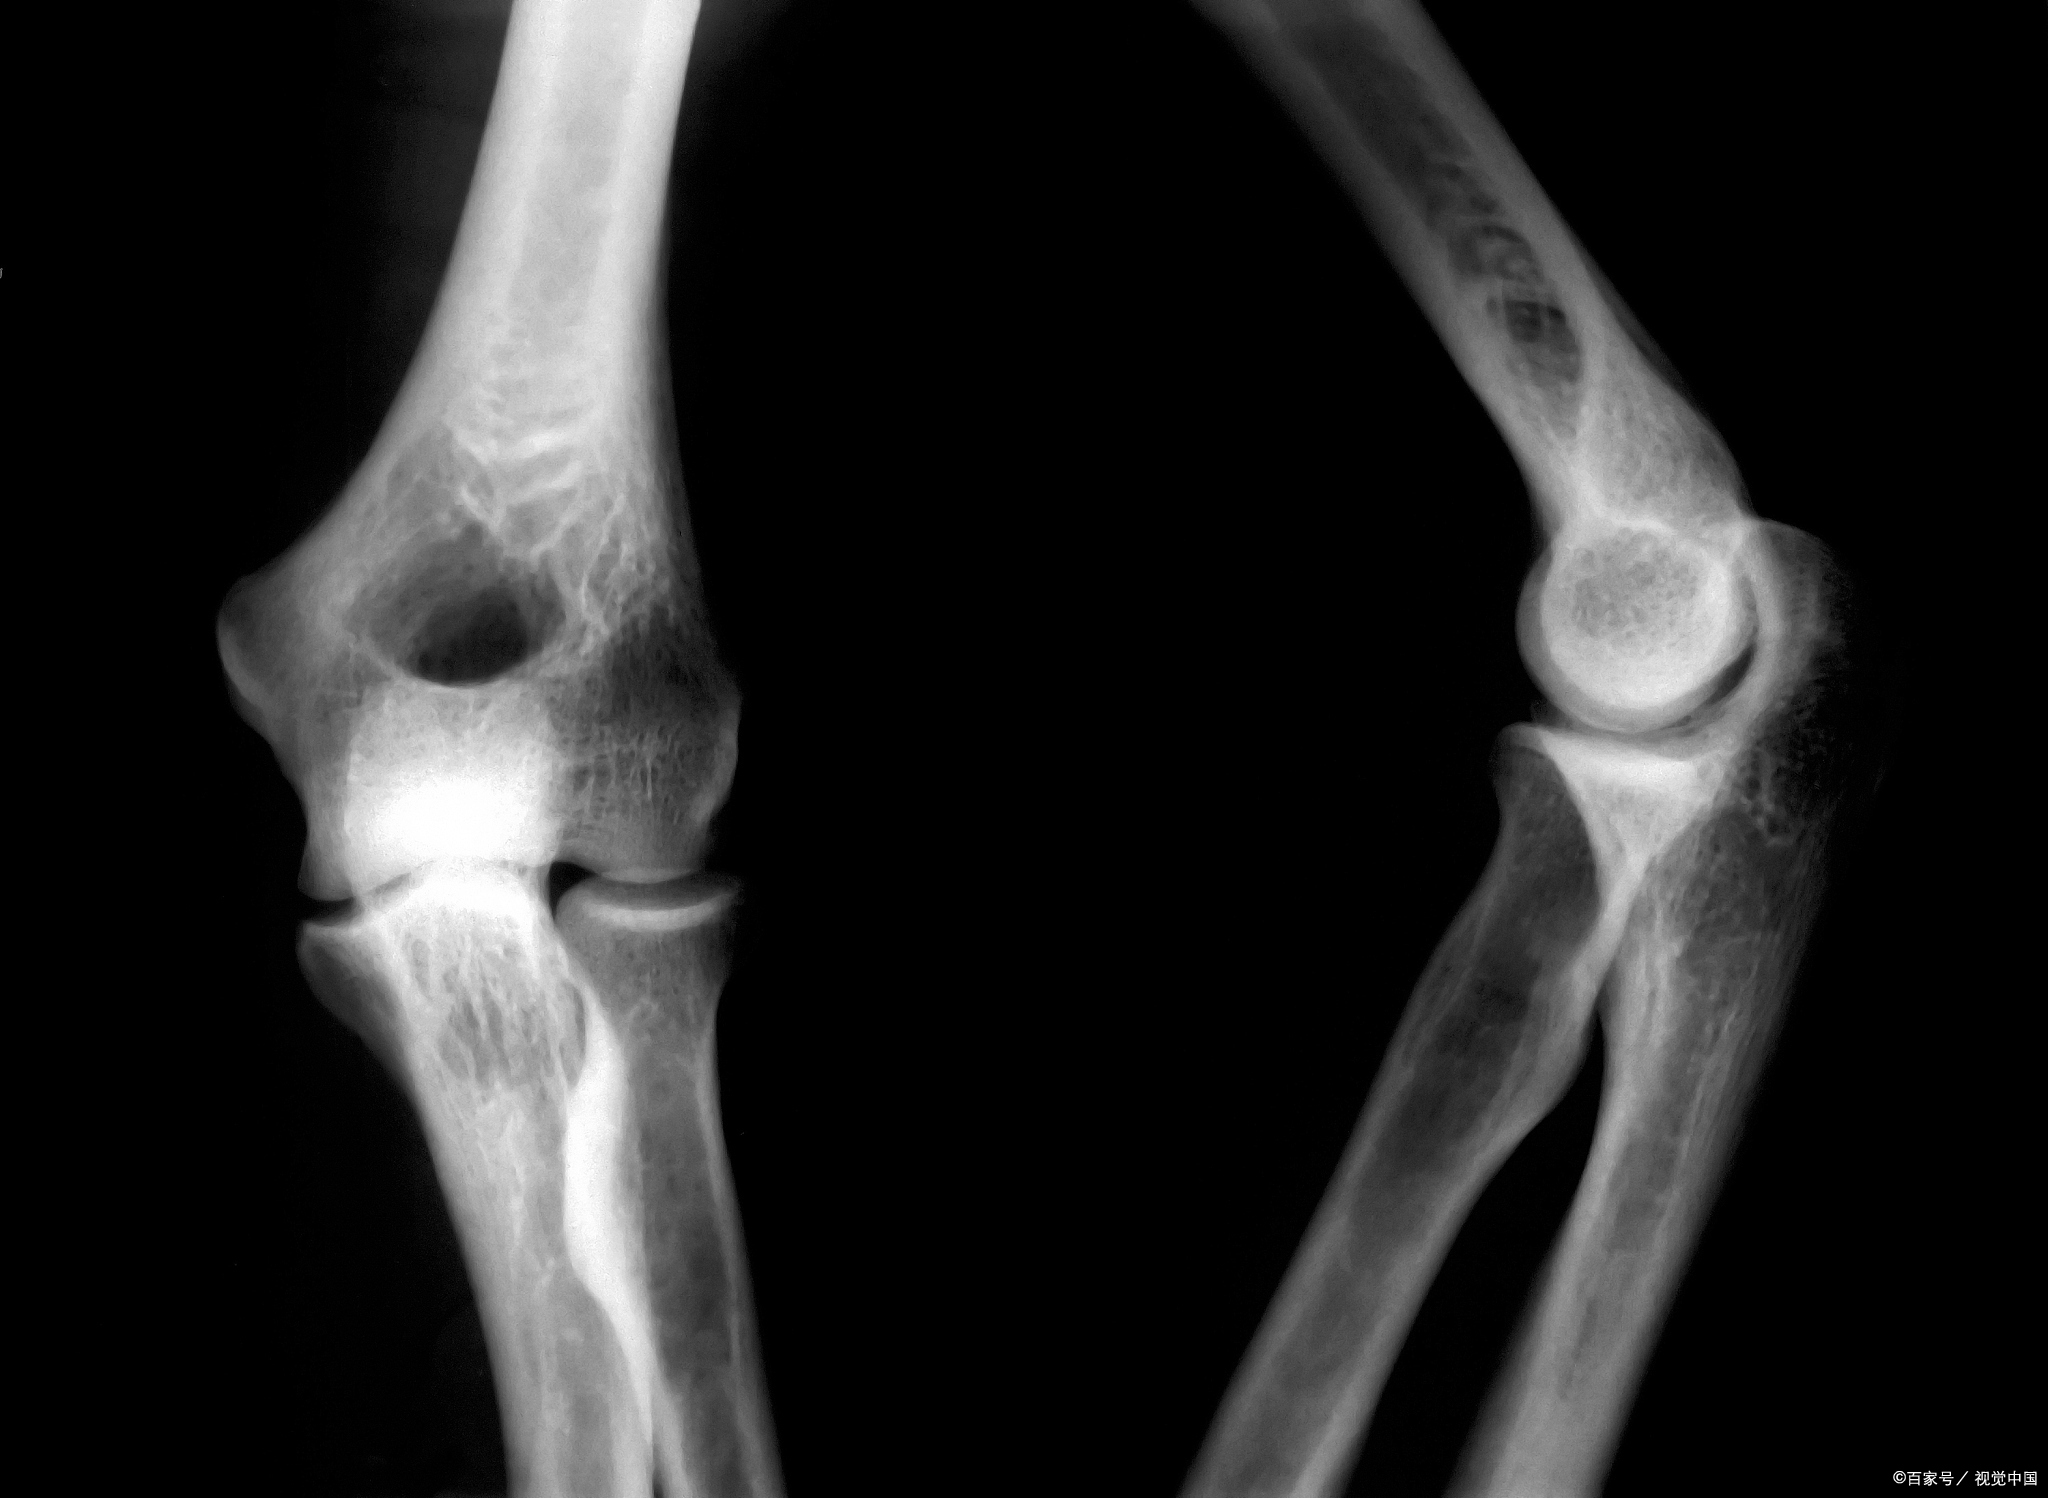

骨骺线是孩子长高的生命线,如果它闭合后孩子不能长高,骨骺线的发育与骨龄密切相关,骨骺线是骨骺与干骨骺端之间的软骨,在X线检查时,会呈现出较宽的透光带。

随着年龄的增长,骨骺线逐渐钙化。当它完全钙化时,骨骺线完全闭合,没有生长空间。